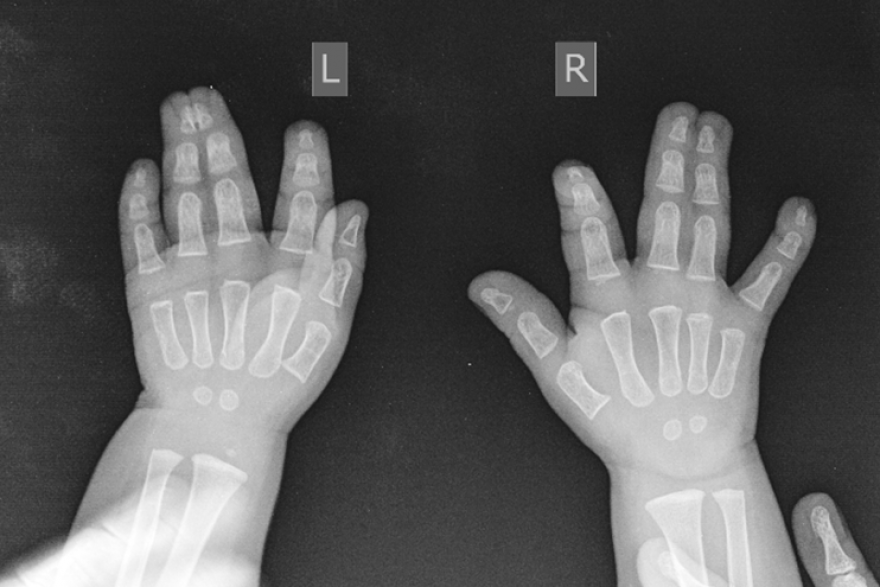

Синдактилия, так называется данное генетическое заболевание, у малыша была на обеих руках. В октябре ему предстоит операция на правой. Это вмешательство менее сложное, говорят врачи - ведь на этой руке срослись только кожные ткани, а вот на правой пришлось разделять ещё и кости.

В курганском центре синдактилию лечат методом, который основан на разработках Гавриила Абрамовича Илизарова. Метод аккредитовали в 2007 году. С помощью этого метода врачам не нужно брать кожу с донорских областей тела, ведь необходимую ткань наращивают аппаратом Илизарова прямо на руке пациента.

- Мы используем детали мини-аппарата Илизарова. У таких пациентов накладываем аппарат на кисть и за счёт открытия, сделанного Илизаровым, начинаем растягивать ткань в определенном темпе. Тем самым мы добиваемся того, что вырастает кожа, и нам не требуется уже потом для формирования после разъединения пальцев брать кожу с донорских участков, - рассказывает заведующий травматолого-ортопедическим отделением № 13 центра Илизарова Денис Тягунов .

Лечение проходит в два этапа. Первый - формирование донорской ткани при помощи установки аппарата Илизарова - длится в среднем 1,5 месяца. Второй - само разъединение. Длительность операции зависит от особенностей каждого пациента - в среднем, это несколько часов.

- Прислать не просто свои «пожелания» у нас прооперироваться, а чтобы не втягиваться в долгую переписку, желательно прислать фото или видеофайл с функцией кисти, желательно. И рентгенограмму кисти в двух проекциях, давностью не более месяца, - уточняет Денис Тягунов .